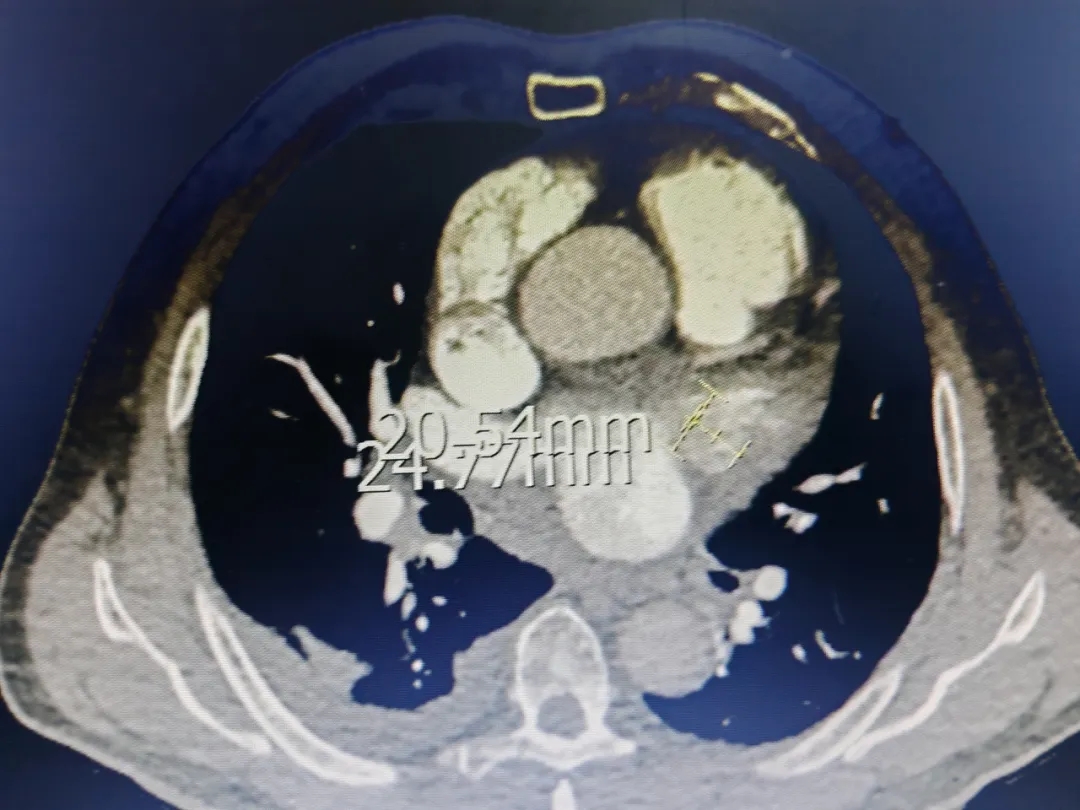

术前检查:心脏CT测量开口直径

CT二维测量开口20.54mm